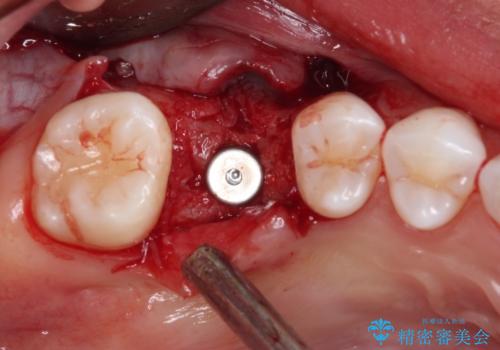

抜歯前のCTにより、インプラントを埋入するために必要な歯槽骨量が不足することが予想されたため、サイナスソケットリフトにより上顎洞内の粘膜を挙上して、インプラントを埋入することとしました。

その後は、オールセラミッククラウンにて補綴することとしました。

虫歯を放置した期間が長かったため、対合の下顎大臼歯が上顎に迫ってきており、咬み合わせは非常にシビアでした。

仮歯装着中に頻繁に脱離したため、オールセラミッククラウンは脱離の少ないスクリュータイプとしました。